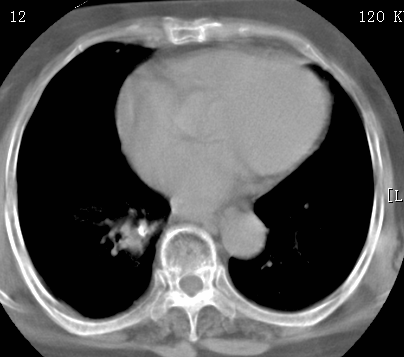

标题: CT26680:肺部右下肺静脉干结节的界定 [打印本页]

标题: CT26680:肺部右下肺静脉干结节的界定

增强适应症

考虑1、周围型肺癌,2肺静脉畸形,前者可能大,建议增强检查。

考虑1、周围型肺癌,2肺静脉畸形,前者可能大,建议增强检查。支持!

不排除右肺下叶周围型肺癌可能。

中心型肺癌,纤支镜可帮助明确。